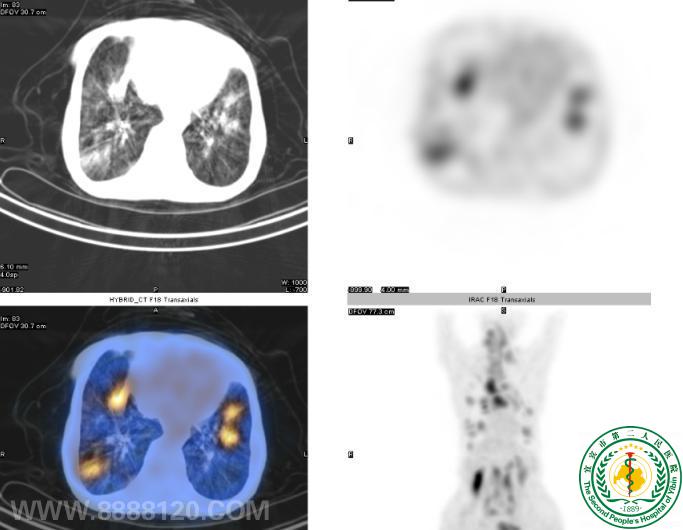

“鹰眼PET/CT”发现结肠Ca术后多处转移一例

“鹰眼PET/CT”发现结肠Ca术后多处转移一例6504